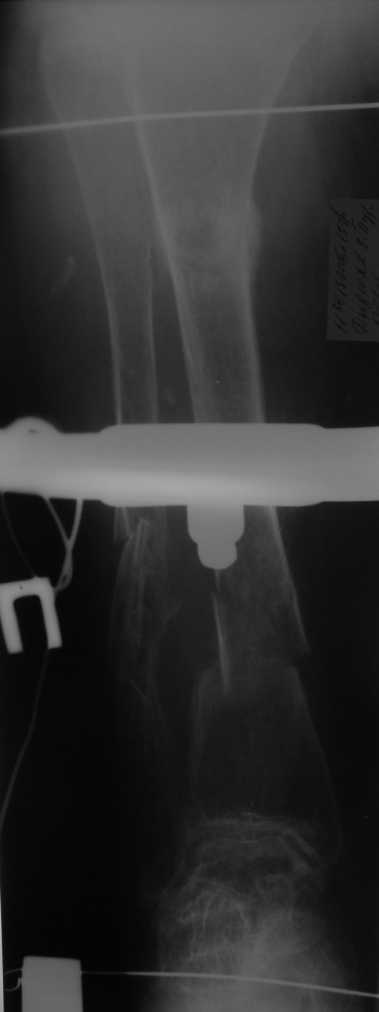

Re: Множественные переломы нижних коенечностей на фоне деформаций

Но даже при малоинвазивной методике лечения применимой для даной больной существуют следующие проблемы: выраженный остеопороз, тонкий кортикал, очень широкий канал.

Контрольные рентгенограммы прилагаю.